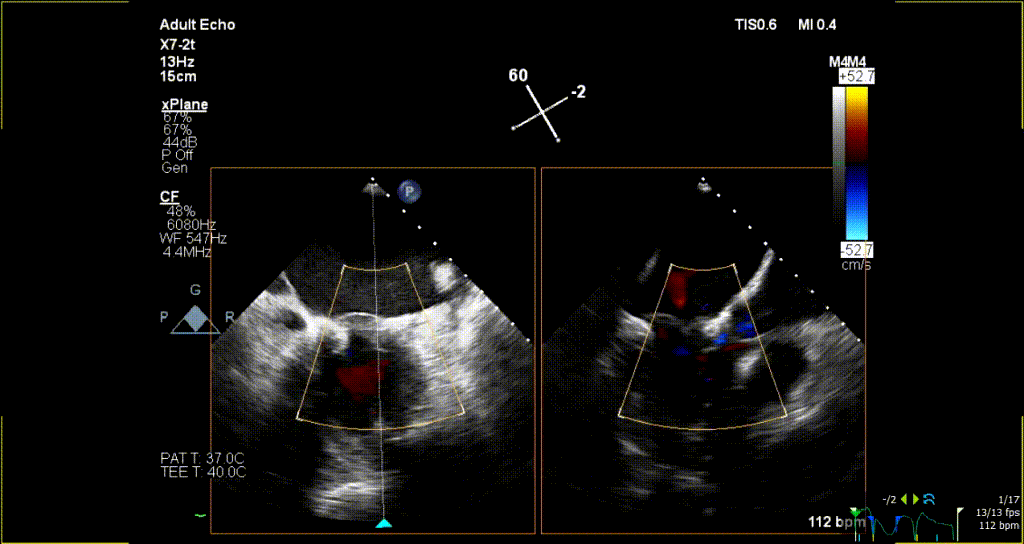

术后超声评估:

术后无反流、左室流出道通畅